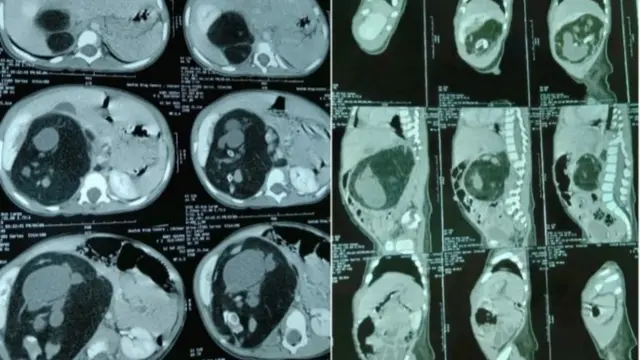

"બાળકનું સીટી સ્કૅન કરાવ્યું તો ખબર પડી કે બાળકી પાંચ લાખમાં એક બાળકને થતા 'ફીટસ ફિતુ' રોગનો શિકાર થઈ છે."

ઑપરેશન અંગેની વિગત આપતાં ડૉક્ટર રાકેશ જોશી કહે છે, "18 મહિનાની વેદિકા અમારી પાસે આવી ત્યારે તેના શરીરમાં રહેલો ગર્ભ 400 ગ્રામનો થઈ ગયો હતો. સામાન્યપણે લોકો એવું માનતા હોય છે કે ફીટસ ફિતુમાં બાળકીના ગર્ભાશયમાં ગર્ભ હોય છે પણ એવું નથી હોતું એ ગર્ભાશયની બહારના ભાગમાં વિકસે છે."

તેઓ આગળ કહે છે કે, "વેદિકાના પેટના ભાગમાં આ ગર્ભ વિકસી રહ્યો હતો અને તે લીવર અને કિડની પર અસર કરી રહ્યો હતો, કારણ કે એ ગાંઠની જેમ વિકસે છે."

ગર્ભની ગંભીર અસરો અને ઑપરેશનની ગંભીરતા વિશે વાત કરતા ડૉ. જોશી કહે છે, "આ વિકસિત ગર્ભ કિડનીની નળી, લીવરની નસો પર અસર કરતો હોય છે જેથી બાળક પૂરતો ખોરાક લઈ શકતું નથી. એને પેશાબની તકલીફ થાય છે. આ ઑપરેશન વાસ્તવમાં ઘણું જોખમી હોય છે."

તેઓ આગળ કહે છે, "અમે જોયું કે બાળકનું હિમોગ્લોબિન બરાબર છે એટલે એના ઑપરેશનની તૈયારી કરી લીધી. ઍનેસ્થેટિસ્ટને સાથે રાખી કિડની, કરોડરજ્જુ અને લીવરને દબાવતો આ અવિકસિત ગર્ભ સાડા ત્રણ કલાકના ઑપરેશન બાદ દૂર કરી નાખ્યો."

ડૉક્ટર રાકેશ જોશી આ પ્રકારની ગાંઠ અંગે વધુ સમજ આપતાં કહે છે કે, "આવા કેસમાં જે ગર્ભ વિકસે છે એ ગાંઠ જેવો હોય છે. જે તમને સીટી સ્કૅનમાં બાળક વિકસતું હોય એવું જ લાગે પણ એનાં ફેફસાં, મગજ કે બીજાં અંગોના કોષો કામ કરતા નથી હોતા એટલે એ એક પ્રકારની ગાંઠ જેવું હોય છે."